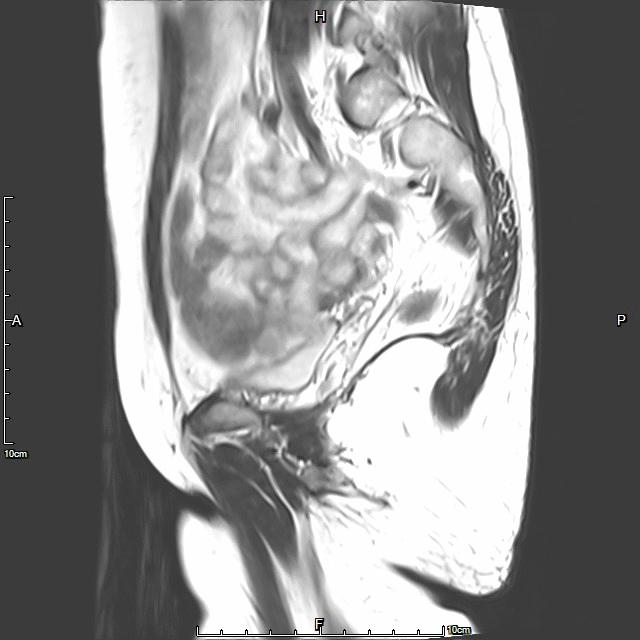

- 术前彩超、磁共振检查显示子宫明显增大,子宫前壁可见弥漫型子宫腺肌症病灶,合并粘膜下、肌壁间子宫肌瘤。

横断位

冠状位

矢状位